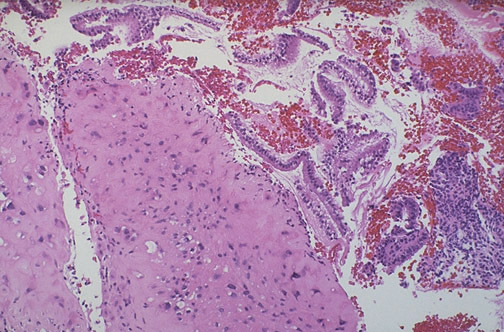

| This rare form of gestational trophoblastic disease (GTD) is a placental site nodule (placental site plaque). This lesion is composed of a small proliferation of intermediate trophoblast. It is of no real consequence, but it must be distinguished from other forms of GTD. |